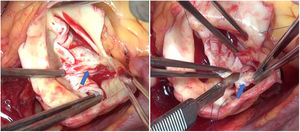

En la VAB con frecuencia hay que tratar el prolapso de los velos. En muchos pacientes el velo anterior está elongado e induce prolapso del mismo. En estos casos la plicatura del borde libre permite elevar e igualar ambos velos, consiguiendo una buena coaptación1. En otras ocasiones, encontramos velos rígidos, con calcificación y restricción a la apertura del velo. En esos casos se puede resecar el rafe que está produciendo esa retracción y decalcificar el velo, para poder ganar movilidad (figuras 1 y 2).

La laxitud y fragilidad de los tejidos hace que haya que prestar especial atención a algunos detalles técnicos durante la cirugía de preservación valvular aórtica en estos pacientes. En nuestra experiencia, para el reimplante usamos puntos de Ti-Cron 2/0 apoyados en teflón en el plano subvalvular. El uso del teflón sirve para evitar el desgarro de los tejidos. Asimismo, hay que recordar que el objeto de estas suturas es sujetar la prótesis al anillo dándole estabilidad, por lo que se debe anudar suavemente. En la porción membranosa del septo, el punto del anillo se da sin teflón y un poco más alto, para evitar dañar el velo y el sistema de conducción (figuras 3 y 4).

Inserción de los puntos de anillo en una válvula aórtica tricúspide en un paciente con síndrome de Marfan.

Se muestra en la imagen el anillo de una válvula aórtica tricúspide en un paciente con síndrome de Marfan. Marcamos con dermográfico la zona correspondiente al septo interventricular donde hay mayor riesgo de daño al tejido de conducción. Se observa cómo el punto de anillo a ese nivel se realiza más cerca de la comisura y sin parche.